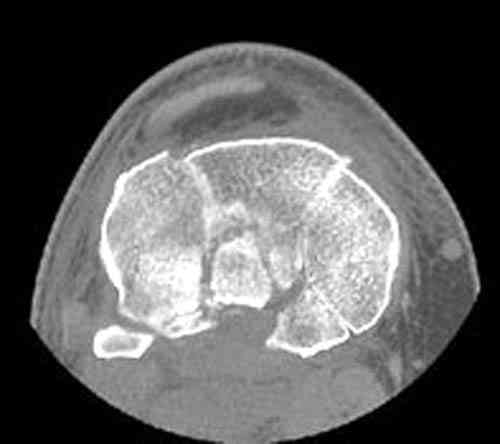

Для определения доступа сагитальные срезы менее информативны, необходимо иметь корональные срезы.

Корональные срезы дают информацию об апексе перелома, и также информацию о вовлечения суставной поверхности, что является немаловажным для прогноза.

Для фиксации переломов тибиал плато обычно применеяется техника создания buttress, пластинами с угловой стабильностью, но в данном случае эпифизарный фрагмент очень тонкий на всем протяжении и фиксировать такой перелом невозможно обычными традиционными методами фиксации.

Для лечения таких эпифизарных переломов применяется техника "создания исскуственного края тибиал плато".

Изгибаясь по контуру медиального эпифиза полу-или 1/3 тубулярные пластины создают медиальный край большеберцовой кости.

Радиально проведенные, через пластину и в эпихондральной зоне (пластина действует как шайба) тонкие 2.7 или 3.5 мм кортикальные шурупы до латерального кортекса создают адекватную фиксацию.